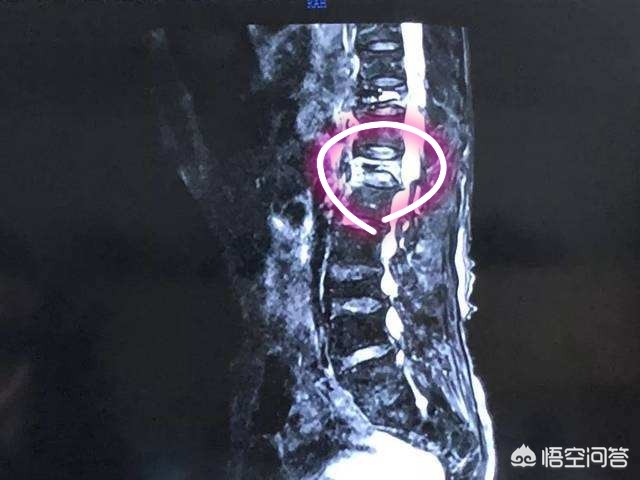

第三,椎管狭窄的患者不适合做燕飞。椎管狭窄的病人,大家从字面上就可以了解到患者椎管已经发生了狭窄。那么此时在做燕飞这样的动作的时候,脊柱是过度向后伸展的,而且我们的头向上抬,脚向上抬,腰椎的压力是比较大的,这样会使本身就已经狭窄的椎管变得更加狭窄,所以说会诱发腰椎管狭窄病人的症状加重。

第四,腰椎间盘脱出的患者不建议做燕飞。腰椎间盘脱出是比较严重的一种腰间盘突出的情况。其实就是腰椎间盘突破了保护它的纤维环掉入到了椎管内。此时不建议做燕飞和腰椎管狭窄患者,不建议做燕飞的道理是一样的。